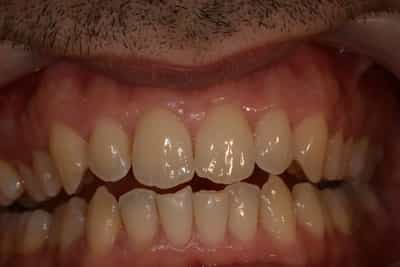

Situation Initiale